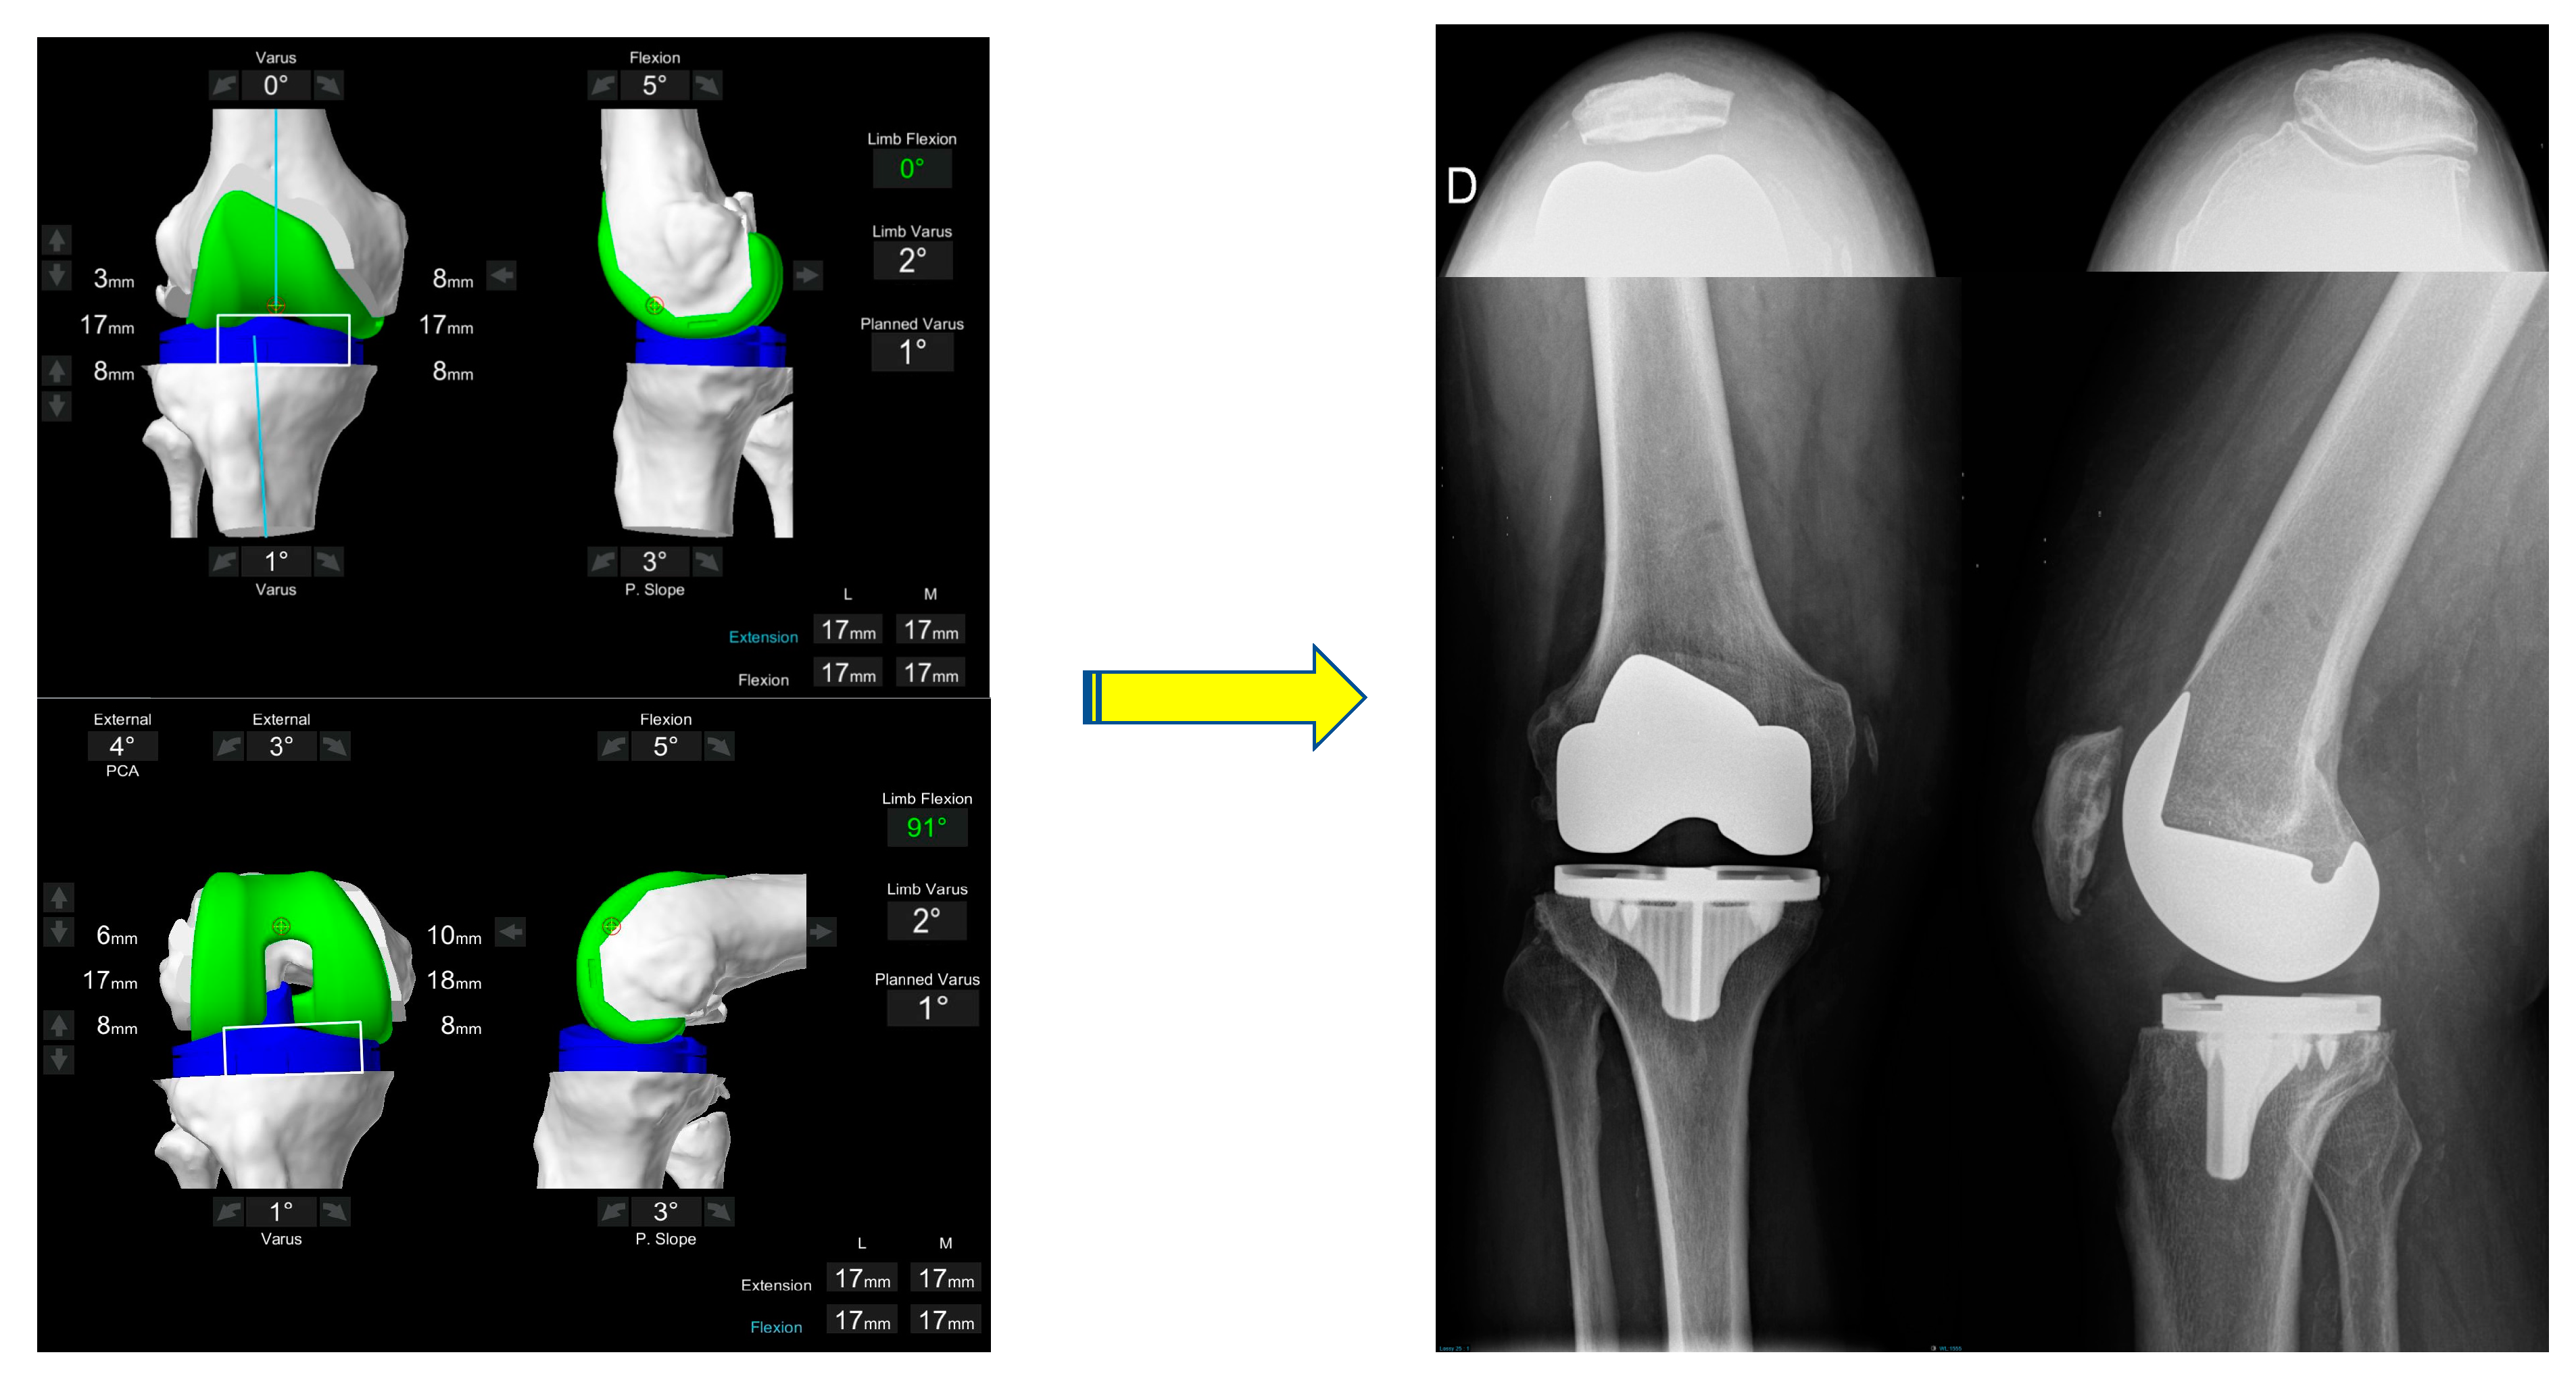

Functional Alignment Philosophy in Total Knee Arthroplasty—Rationale and Technique for the Valgus Morphotype Using an Image Based Robotic Platform and Individualized Planning

2.1. Individualized Pre-Operative Planning

2.1.1. Femur

- Size: posterior referencing with the smallest size that does not overhang mediolaterally, does not notch the anterior femur and avoids overstuffing the patellofemoral joint.

- Coronal plane: femoral implant positioning is planned according to the LDFA with an upper limit of 6° mechanical valgus in femur. To achieve a final alignment with a maximum valgus of 183°, varus positioning on the tibia may be required unless there is extra-articular varus deformity in either the femur or tibia.

- Sagittal plane: femoral component is positioned to achieve the best match possible to the concentricity of Blumensaats line in cases without trochlea dysplasia and to avoid femoral notching. This minimizes patellofemoral over or under stuffing.

- Axial plane: In the valgus morphotype, the posterior lateral femoral condyle is often deficient, making the posterior condylar axis an unreliable landmark for rotation [38]. For this reason, femoral component rotation is planned to balance the flexion space according to the transepicondylar axis (TEA), within a range of 3° internal rotation (IR) to 6° external rotation (ER) to balance the flexion gap. All these adjustments must be made while respecting the alignment with the trochlear groove; care must be taken to assess for trochlea dysplasia which may be present in valgus knees, and if so, recreation of the dysplastic anatomy, such as internally rotating the femur relative to the posterior condylar axis (PCA), should be avoided.

- Resection depth: For distal femoral resection, the medial femoral condyle represents the reference point. A smaller amount of bone is typically removed from the lateral femoral condyle because of wear and morphological variation that is encountered here. It is 9 mm resection if planned from the medial distal femoral condyle and typically 4-6mm from the lateral femoral condyle. The target of 9 mm resection is based on 7 mm of bone plus 2 mm of cartilage.

- Medio-lateral positioning: the lateral patella soft tissue structures are typically tight in a valgus knee, and any medialization of the trochlea groove may exacerbate this and potentially cause patellofemoral dysfunction. However, when using a PS femoral component, care must be exercised that lateralization will not lead to a box cut, which will create a fracture of the lateral femoral condyle due to a thin bony remnant in the lateral column.

2.1.2. Tibia

- Size: The tibia is initially sized with rotation to 0° on the axial view of the CT scan with the aim of having maximal cortical contact with no implant overhang.

- Coronal plane: tibial implant position is aligned to provide the closest match to the medial proximal tibial axis (MPTA) and balance flexion and extension gaps in a range from 2° of valgus to 6° of varus. In the valgus morphotype, in order to avoid a residual valgus HKA > 3° valgus, the tibia is often cut orthogonal to its mechanical axis. A valgus tibial position more than 2° should be avoided. Valgus tibial positioning is reserved for cases where the deformity is an extra-articular tibial deformity, which in our experience is uncommon.

- Sagittal plane: tibial implant position is set to match the patient’s native posterior tibial slope with a limit of 3° when using a PS implant and can be modified to balance the flexion gap if necessary. A limit of 10° combined femoral-tibial flexion is allowed.

- Axial plane: tibial implant is positioned using Akagi’s line. Particular attention should be paid to the avoiding IR of the tibial component, as the valgus morphotype tibia typically falls into ER in deep flexion [36,37] (the position the implant is placed), which promotes the error of internally rotating the tibial baseplate during trials and implantation.

- Tibial resection: 8 mm resection is planned from the medial tibial plateau (6 mm bone + 2 mm cartilage) based on subchondral bone and an average cartilage depth of 2 mm in the normal knee, to use a 9 mm polyethylene insert. Resection from lateral tibial plateau is, typically less i.e., 4–6mm due to wear, but also to account for the extra articular tibial valgus deformity that often co-exists in the valgus morphotype [31]. This gives a combined planned resection of 17 mm medially, which is the combined thickness of this implant with its thinnest tibial liner.